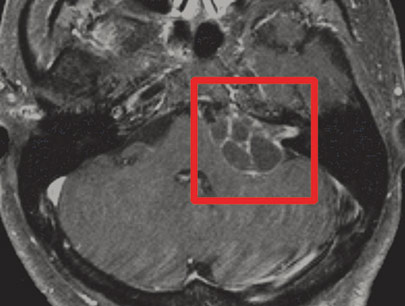

Multiple Metastasis

Radiosurgery adalah tindakan ideal untuk metastasis (anak sebar tumor ganas) ke otak.

Metastasis pada otak dilokalisir dengan baik.

SEBELUM

SESUDAH